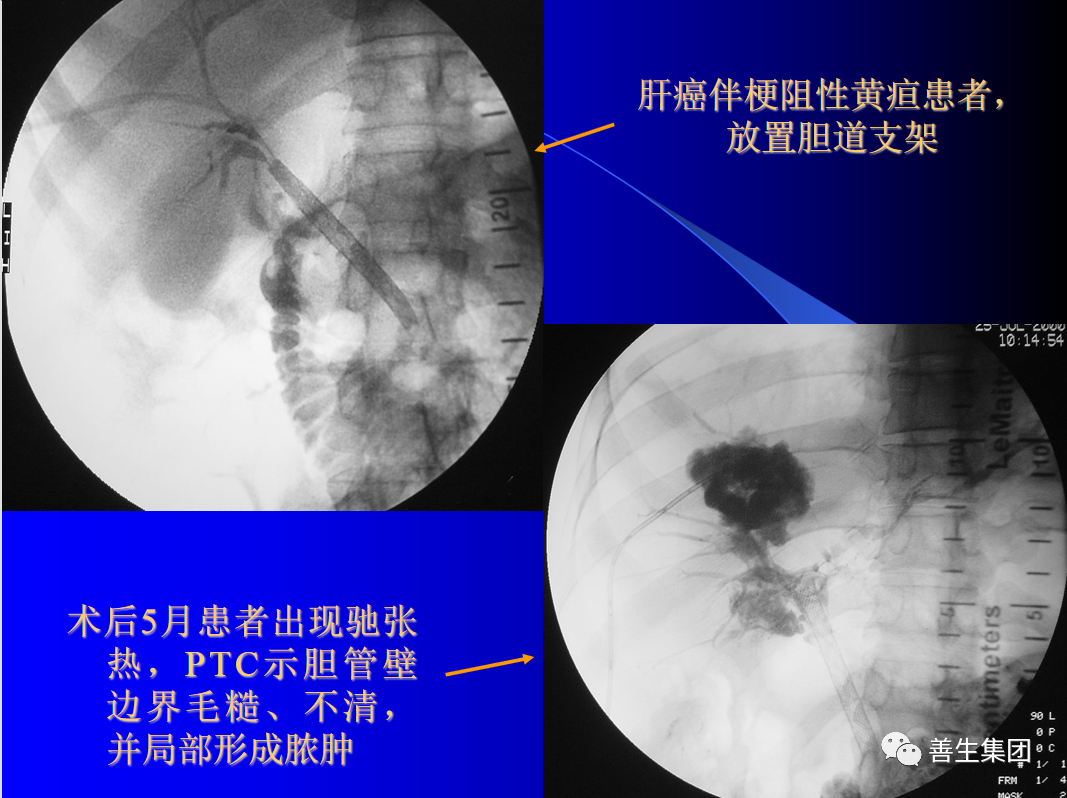

(1) 胆管炎和胆管脓肿是胆管引流最常见的并发症。

皮肤巩膜黄染伴皮肤瘙痒20余日,胰头MT。

胆管支架什么样子经皮肝胆管穿刺置管引流术(PTCD)及胆道内支架临床应用_https://www.jmylbn.com_新闻资讯_第14张

MIR和CT

胆管支架什么样子经皮肝胆管穿刺置管引流术(PTCD)及胆道内支架临床应用_https://www.jmylbn.com_新闻资讯_第15张

PTC造影+MIR胆道